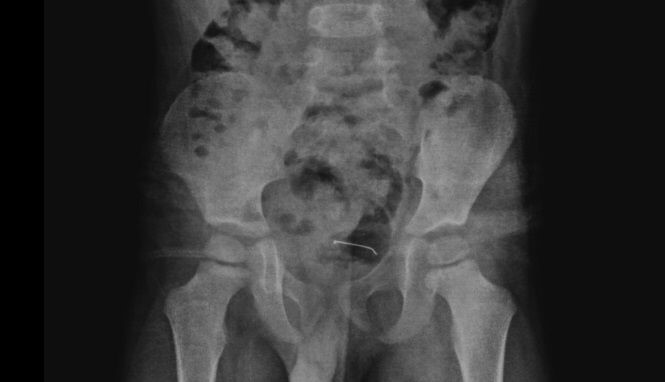

Daha önce farklı sağlık kuruluşlarına başvuran ancak kesin bir sonuç alamayan aile, çocuklarının karın ağrısı şikayetinin artması üzerine Tatvan Devlet Hastanesi Çocuk Cerrahisi Polikliniğine başvurdu. Yapılan röntgen incelemelerinde, mesane duvarında metal bir cisim olduğu tespit edildi.

Uzun süre vücutta kalan 3 santimetrelik toplu iğnenin mesane duvarına yapıştığı belirlendi. Ailenin bilgilendirilmesinin ardından Tatvan Devlet Hastanesi Çocuk Cerrahi Uzmanı Op. Dr. Tahsin Onat Kamçı tarafından gerçekleştirilen operasyonla, toplu iğne başarılı bir şekilde çıkarıldı. Ameliyat sonrası birkaç gün gözlem altında tutulan çocuk, tekrar kontrole gelmek üzere taburcu edildi.

Hastanın kontrollerinde, yuttuğu cismin doğal yollarla vücuttan çıkmadığını tespit ettiklerini anlatan Kamçı, "Bunun üzerine ameliyat kararı aldık. Ameliyatta cismin mesane duvarına yapıştığını gördük. Cerrahi operasyonla 3 santimetre civarındaki toplu iğneyi çıkardık. Hastayı birkaç gün takipte tuttuk. Genel sağlık durumu iyi olan hastamızı taburcu ettik" diye konuştu.